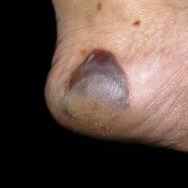

Bullous Diabeticorum. This uncommon cutaneous finding in patients with diabetes is characterized by large, tense noninflammatory subepidermal bullae that usually appear spontaneously on the legs and feet (William Weston Collection).